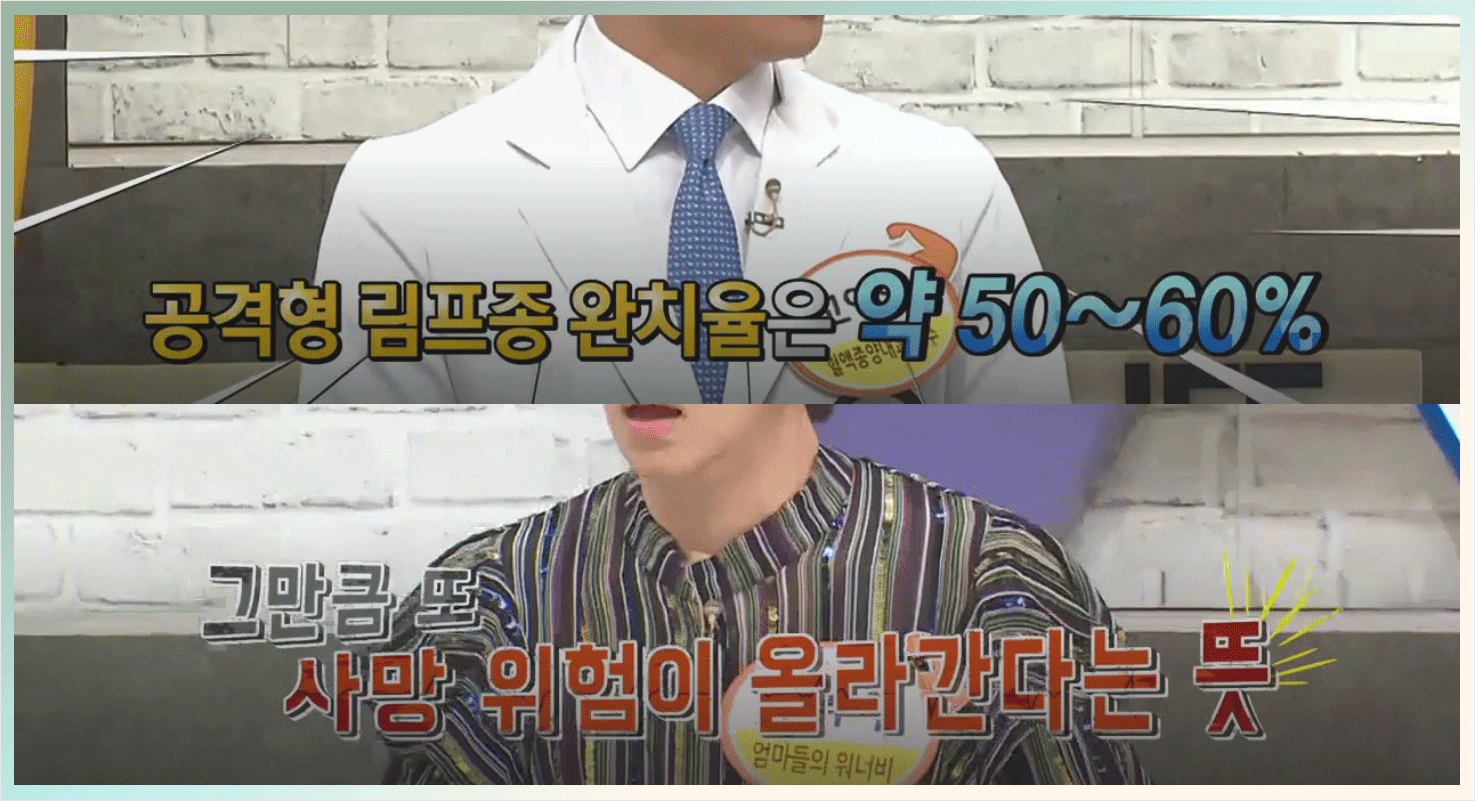

이중에 공격형 림프종은

대략 50에서 60퍼센트의

완치율을 갖게 되지요.

또한 림프종은 주로 수술보다는

항암치료의 비중이 높기 때문에,

완벽한 치료가 불가능할 수 있어요.

그래서 보조적인 식이요법과 환자의

적극성이 큰 영향을 끼친다고 할 수 있죠.